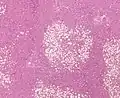

| Micrograph demonstrating marked (macrovesicular) steatosis in non-alcoholic fatty liver disease. Masson's trichrome stain. | |

Histology

Histologically, steatosis is physically apparent as lipid within membrane bound liposomes of parenchymal cells.[2] When this tissue is fixed and stained to be better viewed under a microscope, the lipid is usually dissolved by the solvents used to prepare the sample. As such, samples prepared this way will appear to have empty holes (or vacuoles) within the cells where the lipid has been cleared. Special lipid stains, such as Sudan stains and osmium tetroxide are able to retain and show up lipid droplets, hence more conclusively indicating the presence of lipids. Other intracellular accumulations, such as water or glycogen, can also appear as clear vacuoles, therefore it becomes necessary to use stains to better determine what substance is accumulating.

Histological section of a mouse's liver showing severe steatosis. The clear vacuoles contained lipid in life; however, histological fixation caused it to be dissolved and hence only empty/clear spaces are seen.

Histological section of a mouse's liver showing severe steatosis. The clear vacuoles contained lipid in life; however, histological fixation caused it to be dissolved and hence only empty/clear spaces are seen. Micrograph of fatty liver showing lipid steatosis. H&E stain.

Micrograph of fatty liver showing lipid steatosis. H&E stain. Steatosis with a centrilobular pattern, which is the general tendency for steatosis in adults.[11]

Steatosis with a centrilobular pattern, which is the general tendency for steatosis in adults.[11]